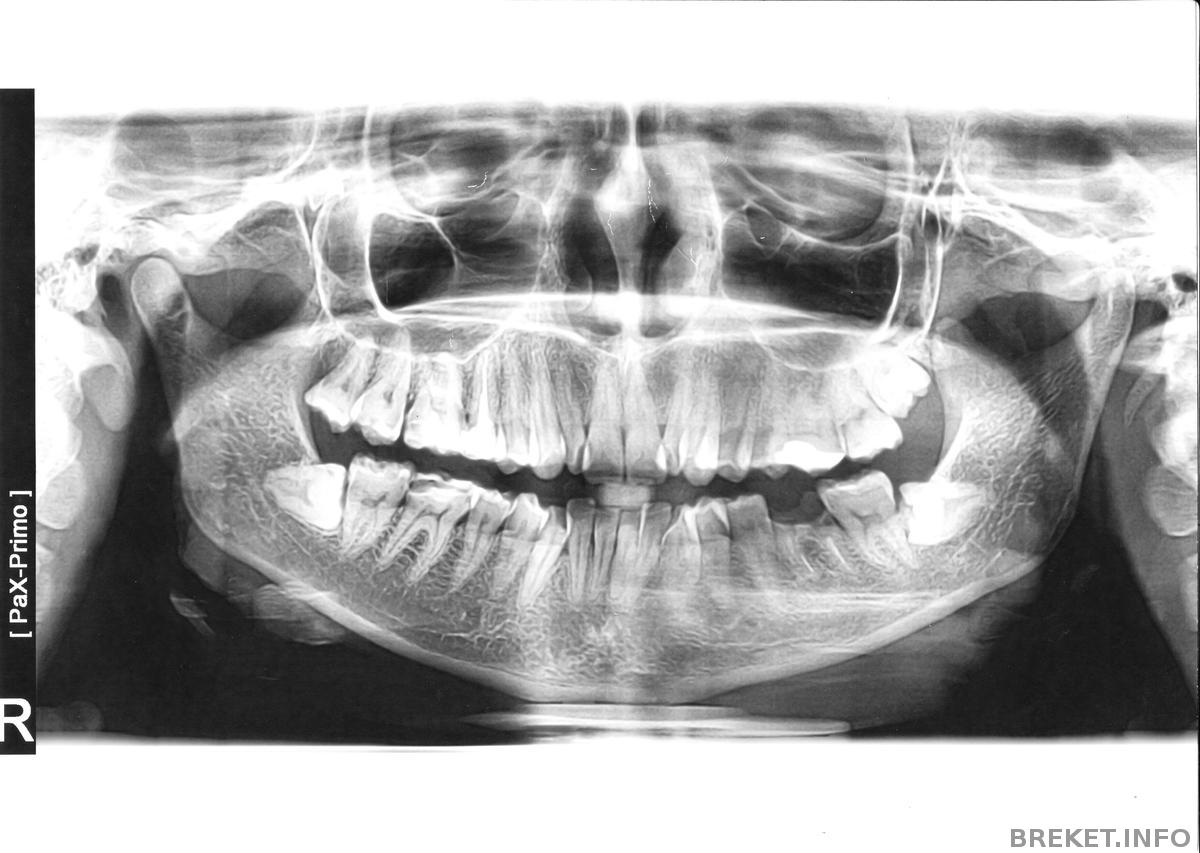

коллаж надо бы сделать ха ха ха из панорамных снимков))))))))))))))

на первом снимке НЧ без дуги, следовательно снимали.